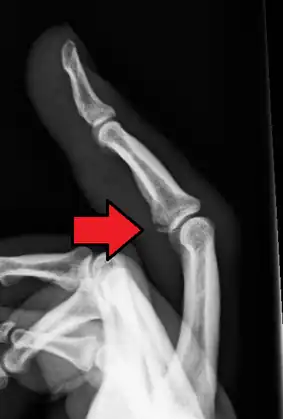

Avulsion fracture of a fingertip bone

Avulsion fracture is a bone fracture which occurs when a fragment of bone tears away from the main mass of bone as a result of physical trauma. This can occur at the ligament by the application of forces external to the body (such as a fall or pull) or at the tendon by a muscular contraction that is stronger than the forces holding the bone together. Generally muscular avulsion is prevented by the neurological limitations placed on muscle contractions. Highly trained athletes can overcome this neurological inhibition of strength and produce a much greater force output capable of breaking or avulsing a bone.

The evaluation of avulsion fractures is generally done via Xrays.[6]